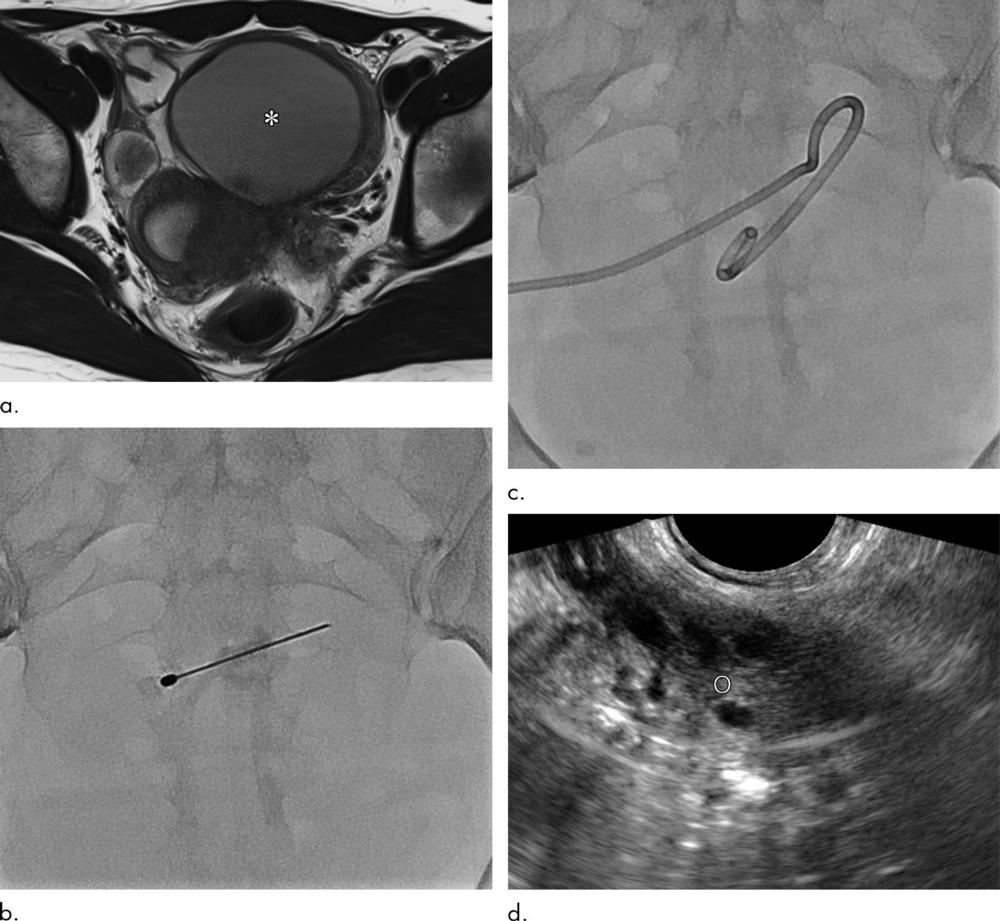

Figure 2. Clinical course of a 27-year-old woman with primary ovarian endometrioma presenting with dysmenorrhea. (a) Axial T2-weighted image reveals an 8.4-cm, multilocular endometrioma (∗) with internal septation (arrows). (b) The endometrioma was punctured and mechanical breakdown of the internal septa was performed. (c) A catheter was inserted and contrast agent was injected to observe for any leakage. (d) Follow-up ultrasound 6 months after catheter-directed sclerotherapy shows markedly decreased endometrioma (∗) size (1.4 cm).

High-res (TIF) version